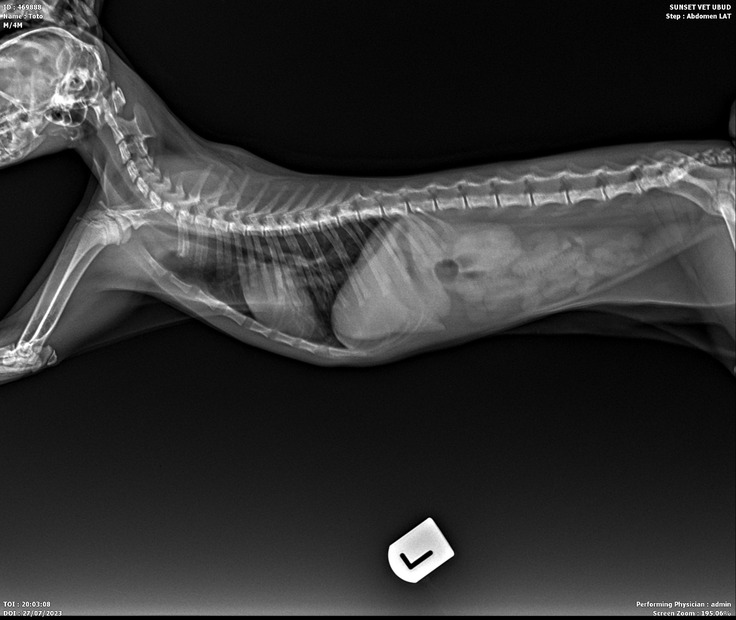

トトくん入院中。

五月ちゃんのおチビちゃんのトトくんが7月27日から入院しています。

サークルの中に入れていたベッドの持ち手の布をを食べて嘔吐。

その後も嘔吐をし病院へ。

レントゲンを撮ってもらった結果、胃の中に異物が残っていて胃から腸まで下りれず、7月29日に開腹手術を致しました。

小さな体で麻酔を心配していましたが、手術も無事に終わり麻酔からも目を覚ましてくれました。

術後の経過も良く、今日から少しずつご飯を口に入れ食べてくれるようになりました。

ひとりでご飯を食べれるようになったら退院出来ると言われていますので、明日か明後日には退院となると思います。

退院後は暫く投薬治療になります。